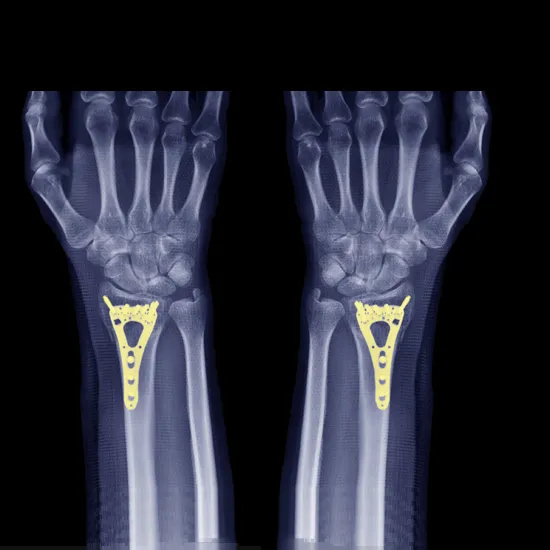

NCCT Left Hand is a plain scan to visualize the left hand including soft tissue and its pathology.

• To detect fracture

In this scan, you need to lie prone on the table and the left hand is placed in the centre of the scanning table and the head can rest on the other arm sides the scans are performed.